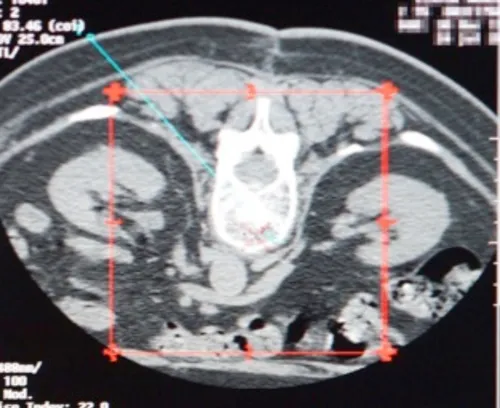

1. Vertèbre cible sur une coupe de scanner — 2. Trait de planification de la ponction sur le scanner de repérage